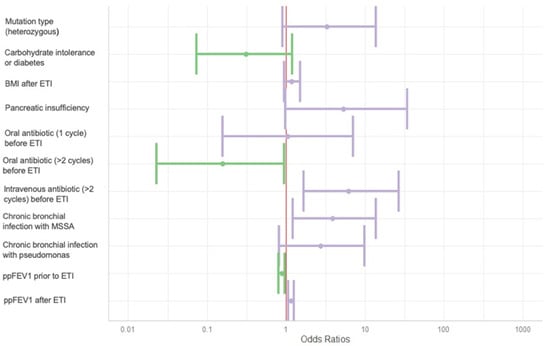

3.5. Factors Influencing the Evolution of the Bhalla Score

In the multivariate analysis (Table 5 and Figure 4), the following variables were independently associated with improvement in the Bhalla score after at least one year of ETI therapy: having received more than two courses of intravenous antibiotics in the year prior to ETI initiation (OR 6.2 [1.7–26.9]); chronic bronchial infection with methicillin-sensitive Staphylococcus aureus (MSSA) (OR 3.9 [1.2–13.7], p = 0.027); and higher ppFEV1, following ETI treatment (OR 1.1 [1.1–1.3], p = 0.002).

Figure 4.

Forest plot of Bhalla score evolution predictors. BMI: body mass index. ETI: elexacaftor–tezacaftor–ivacaftor. MSSA: methicillin-sensitive Staphilococcus aureus. ppFEV1: percentage of predicted forced expiratory volume in the first second. Variables associated with a decline in the Bhalla score are shown in green, while those associated with an improvement are shown in purple.

Conversely, more than two courses of oral antibiotics in the year prior to ETI (OR 0.2 [0.0–0.9], p = 0.047), and lower ppFEV1 before ETI initiation (OR 0.9 [0.8–1.0], p = 0.005) were inversely associated with changes in the Bhalla score.

Other variables assessed, including mutation type, pancreatic insufficiency, and BMI, were not associated with changes in the Bhalla score over time.